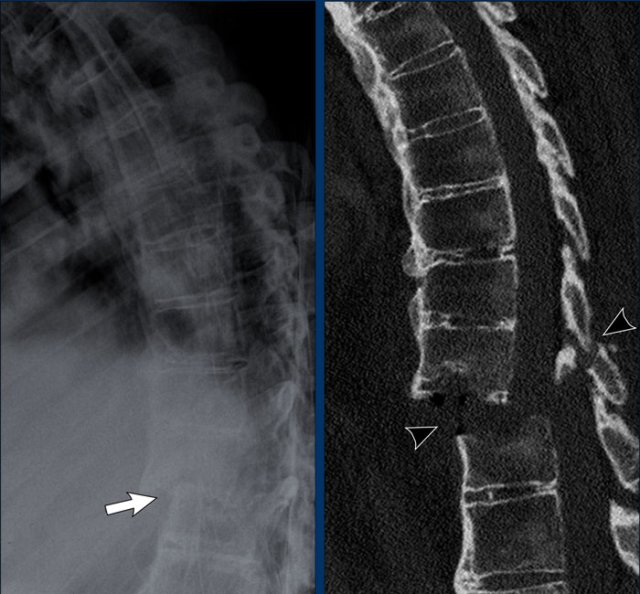

Ankylosing spondylitis Ankylosing spondylitis

Syndesmophytes

These images show syndesmophytes in the lumbar spine and ossification of the paraspinal ligaments.

When these syndesmophytes fuse, this produces the typical “bamboo spine” appearance.

Also note the ossification of the intervertebral disc and ankylosis of the facet joints.

Syndesmophytes have a typically vertical orientation.

Bridging and fusing is quite common.

As a result the spine looses its flexibility and can easily fracture even after a minor trauma.

Bamboo spine

Bamboo spine in ankylosing spondylitis.

Fusion of the lumbar spine by syndesmophytes and ossification of the paraspinal ligaments.

Notice the ligamentous calcification (arrow).

A rigid bamboo spine is prone to hyperextension fractures, even after mild trauma.

Always have a high suspicion of these fractures in a rigid spine!